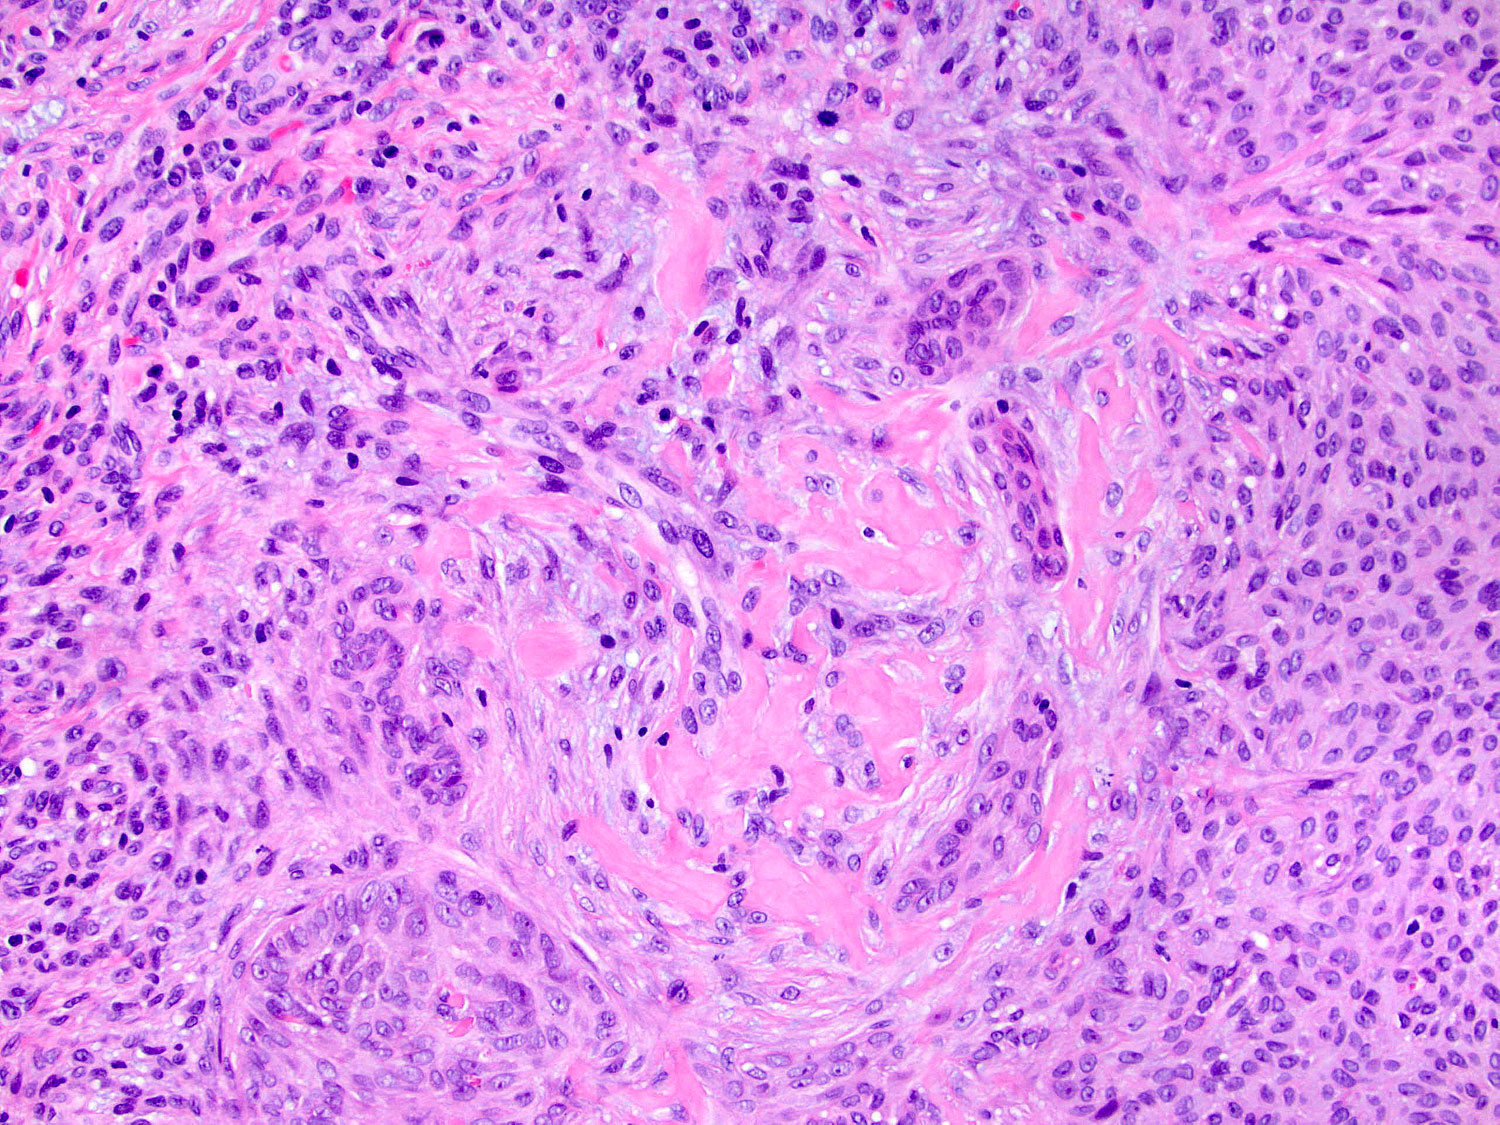

H&E staining (20x objective)